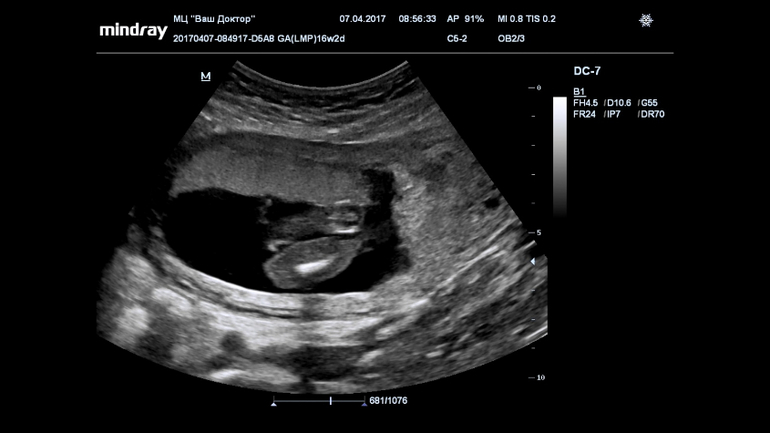

Пол малышаВсе 16 недель была просто уверенна, что в домике живет сыночка, а тут на УЗИ огорошили, что у нас там девица-красавица! Я конечно прибываю в небольшом шоке, но БЕЗУМНО этому рада!!!!!

Записали нам диск, все выходные пересматривала, сделала несколько фото, что скажете?

(фото под кат)...